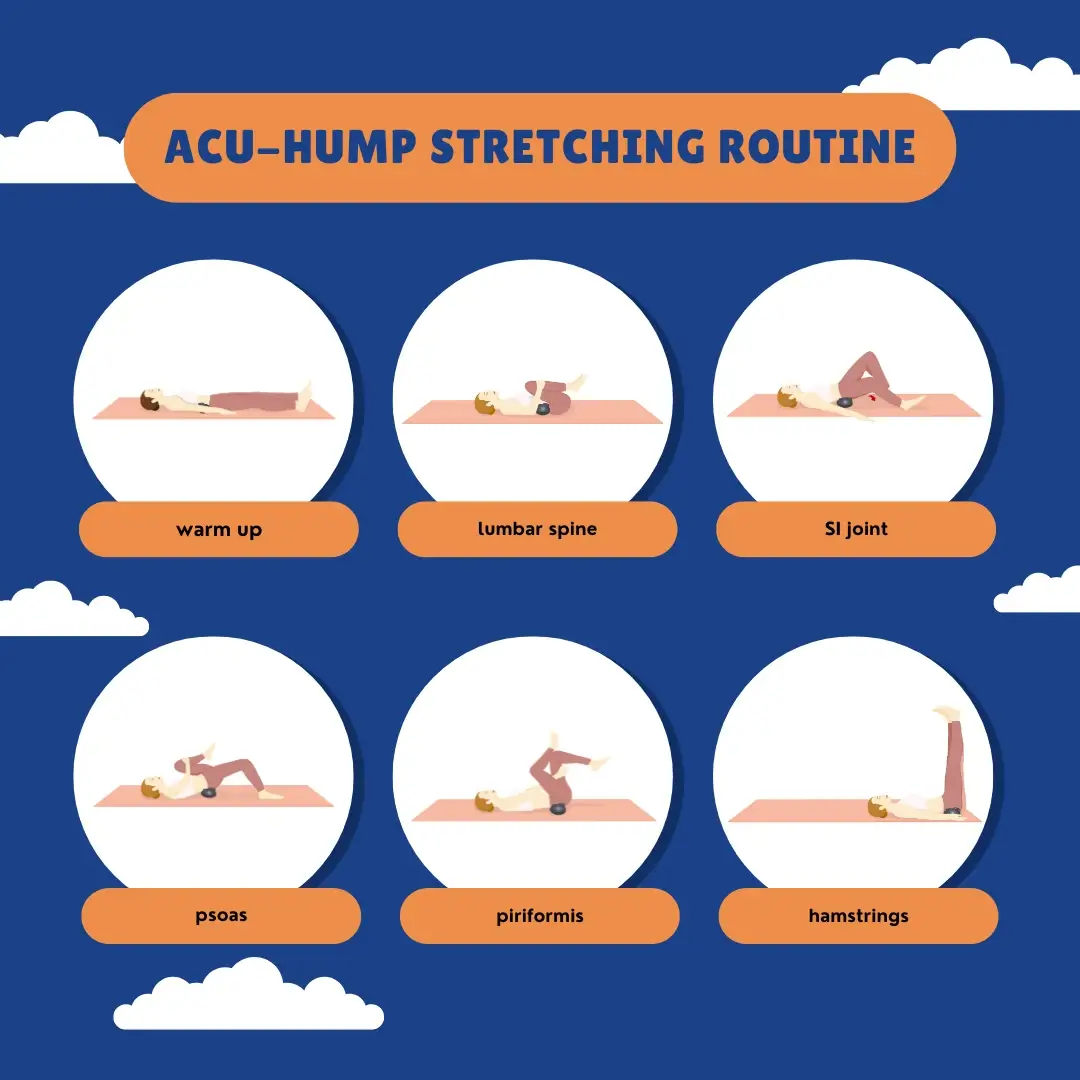

In addition to rest and immobilization, physical therapy is often recommended as an effective treatment for piriformis syndrome.

Physical therapy may involve a combination of exercises to stretch and strengthen muscles in the affected area.

In addition to massage, stretching with Acu-hump can also be incredibly effective for releasing tension in the piriformis muscle. By using the tool to support and extend the muscle, you can work to increase flexibility and reduce the likelihood of injury. Regular stretching exercises can help to prevent the development of piriformis syndrome, while also promoting overall health and well-being.

Save It to Your Phone and View It Anytime

Click to download: 10 Minute piriformis and lumbar pain exercises pdf